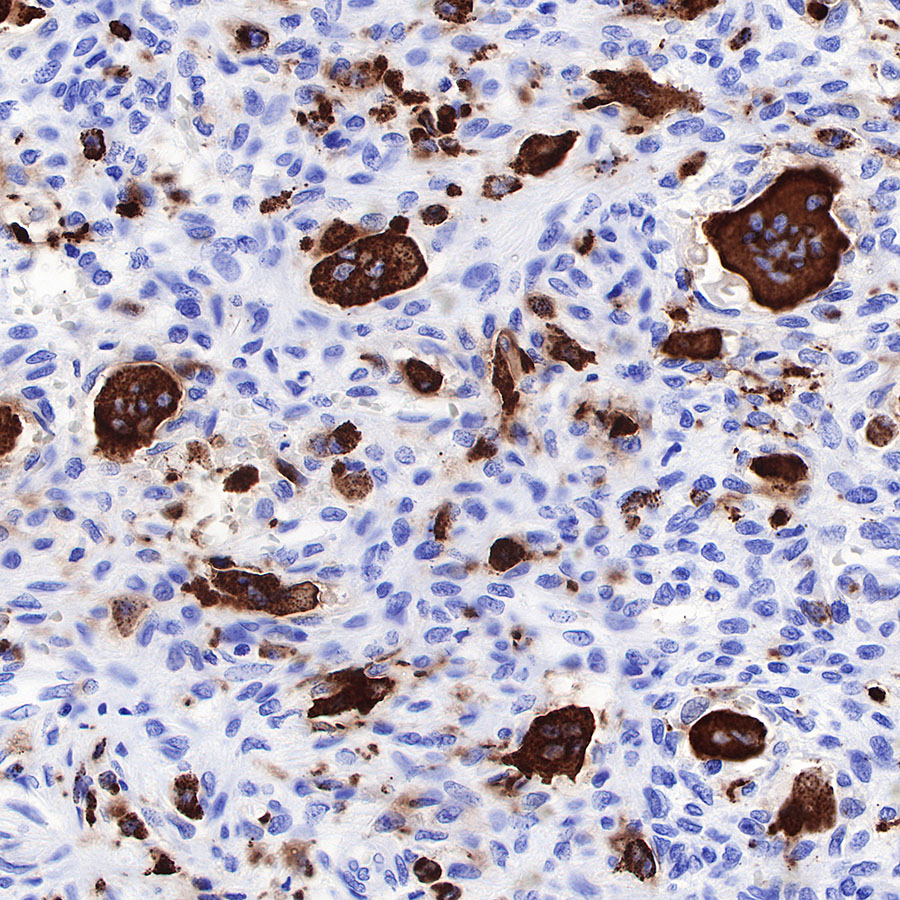

IHC shows positive staining in paraffin-embedded human giant cell tumor of bone. Anti-CD68 antibody was used at 1/1000 dilution, followed by a HRP Polymer for Mouse & Rabbit IgG (ready to use). Counterstained with hematoxylin. Heat mediated antigen retrieval with Tris/EDTA buffer pH9.0 was performed before commencing with IHC staining protocol.